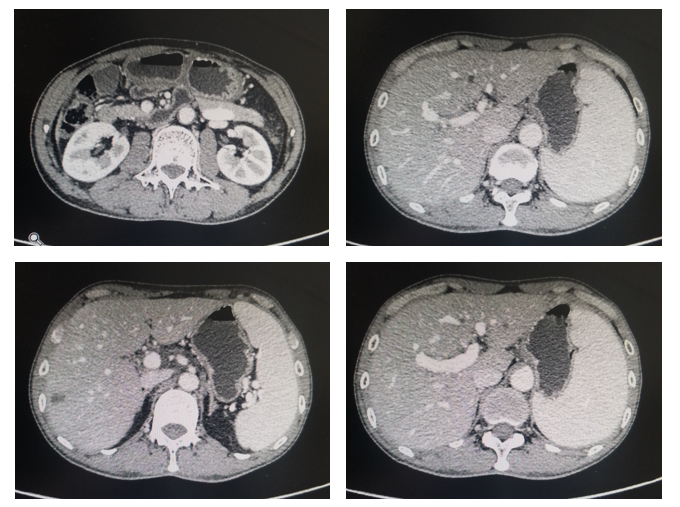

上腹CT:肝内多发低密度结节,胃窦区胃壁增厚(图1)。

评估:治疗后3月和5月复查腹部CT情况(图2和图3).

图3. 腹部CT平扫+强化(治疗后2月,2020年1月)

图4. 腹部CT平扫+强化(治疗后5月,2020年3月)

影像科:根据患者治疗前、治疗后首次及再次复查CT看,原发病灶胃壁增厚明显减轻,肝转移病灶明显缩小,部分病灶消失,首次CT判效PR,再次复查CT确认PR。提示内科治疗有效。

图5. 腹部CT平扫+强化(治疗后7月,2020年5月)